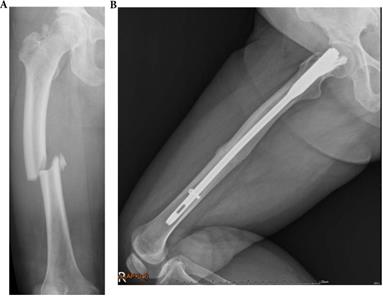

Figure 6

A 61-year-old type 4 OI female suffered a right midshaft femur fracture with intramedullary nailing treatment in August 2018, resulting in non-union. (a) Pre-operation fracture picture (b) Follow up in December 2019.

Int J Med Sci Image

Figure 7

A 29-year-old type 3 OI female suffered a right shaft femur fracture with intramedullary nailing treatment in March 2012, resulting in non-union. (a) Just finished operation in March 2012 (b) Follow up in April 2013.

Influence of treatment on healing rate

In OI type 4, 2 of 5 (40.0%) fractures resulted in non-union. All two patients with type 4 OI who were conservatively treated with OI had shaft fractures resulting in non-unions. Three other patients with type 4 were surgically treated for shaft fractures. All resulted in union (2 IN, 1 PF) (Figures 3, 4, 5). In patients with OI with type 1 OI, 1 of 4 (25.0%) fractures resulted in non-union (Figure 6), for type 3, 1 of 6 (16.7%) fractures resulted in non-union (Figure 7).

Overviewing all shaft fractures (n=9), intramedullary fixated fractures resulted in one non-union of three fractures (33.3%). Plate-fixated fractures resulted in one non-union of three fractures (33.3%). Conservatively treated shaft fractures resulted in two non-unions of three fractures (66.6%).